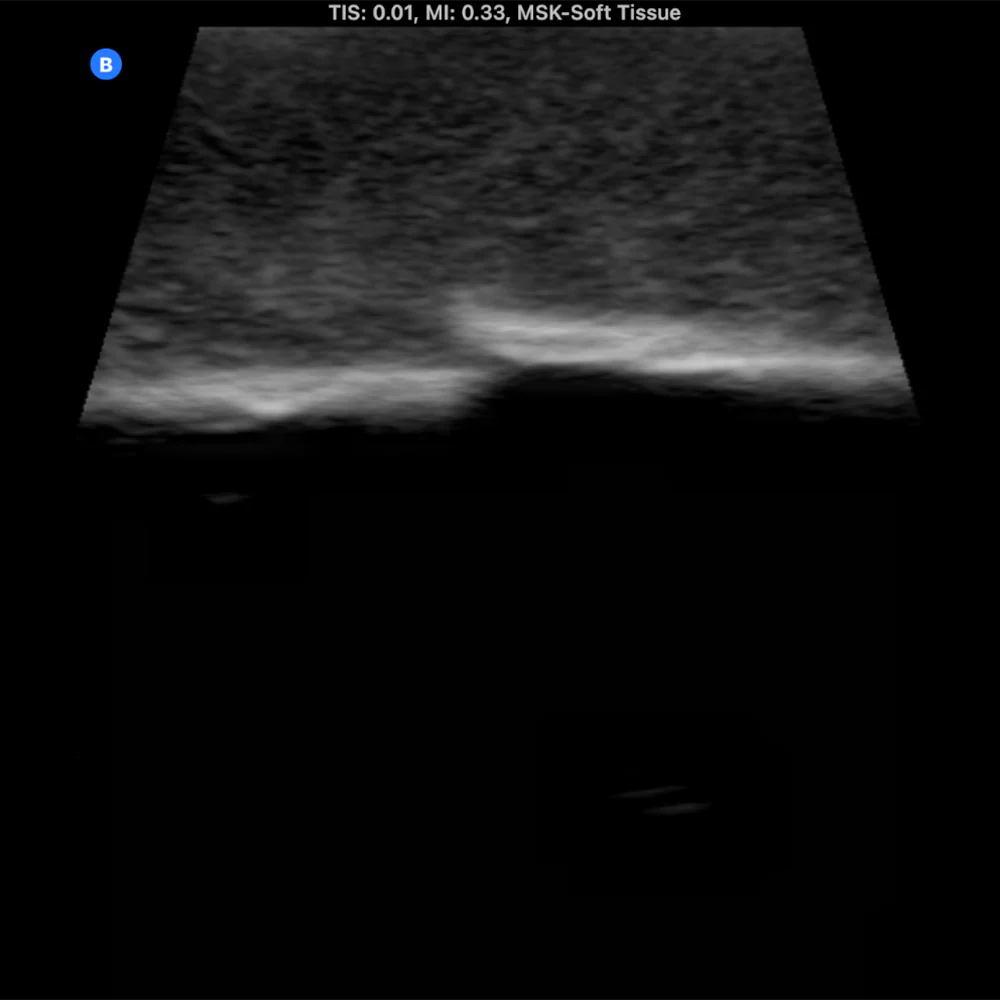

The Bone Fracture Ultrasound Phantom is an excellent training aid for developing the skills needed to identify bone fractures within soft tissue.

- Five bones incorporated within the model (three positioned superficially and two at a deeper level).

- One healthy bone with no fracture, plus four bones featuring fractures of varying severity.

- Produces outstanding ultrasound image quality.